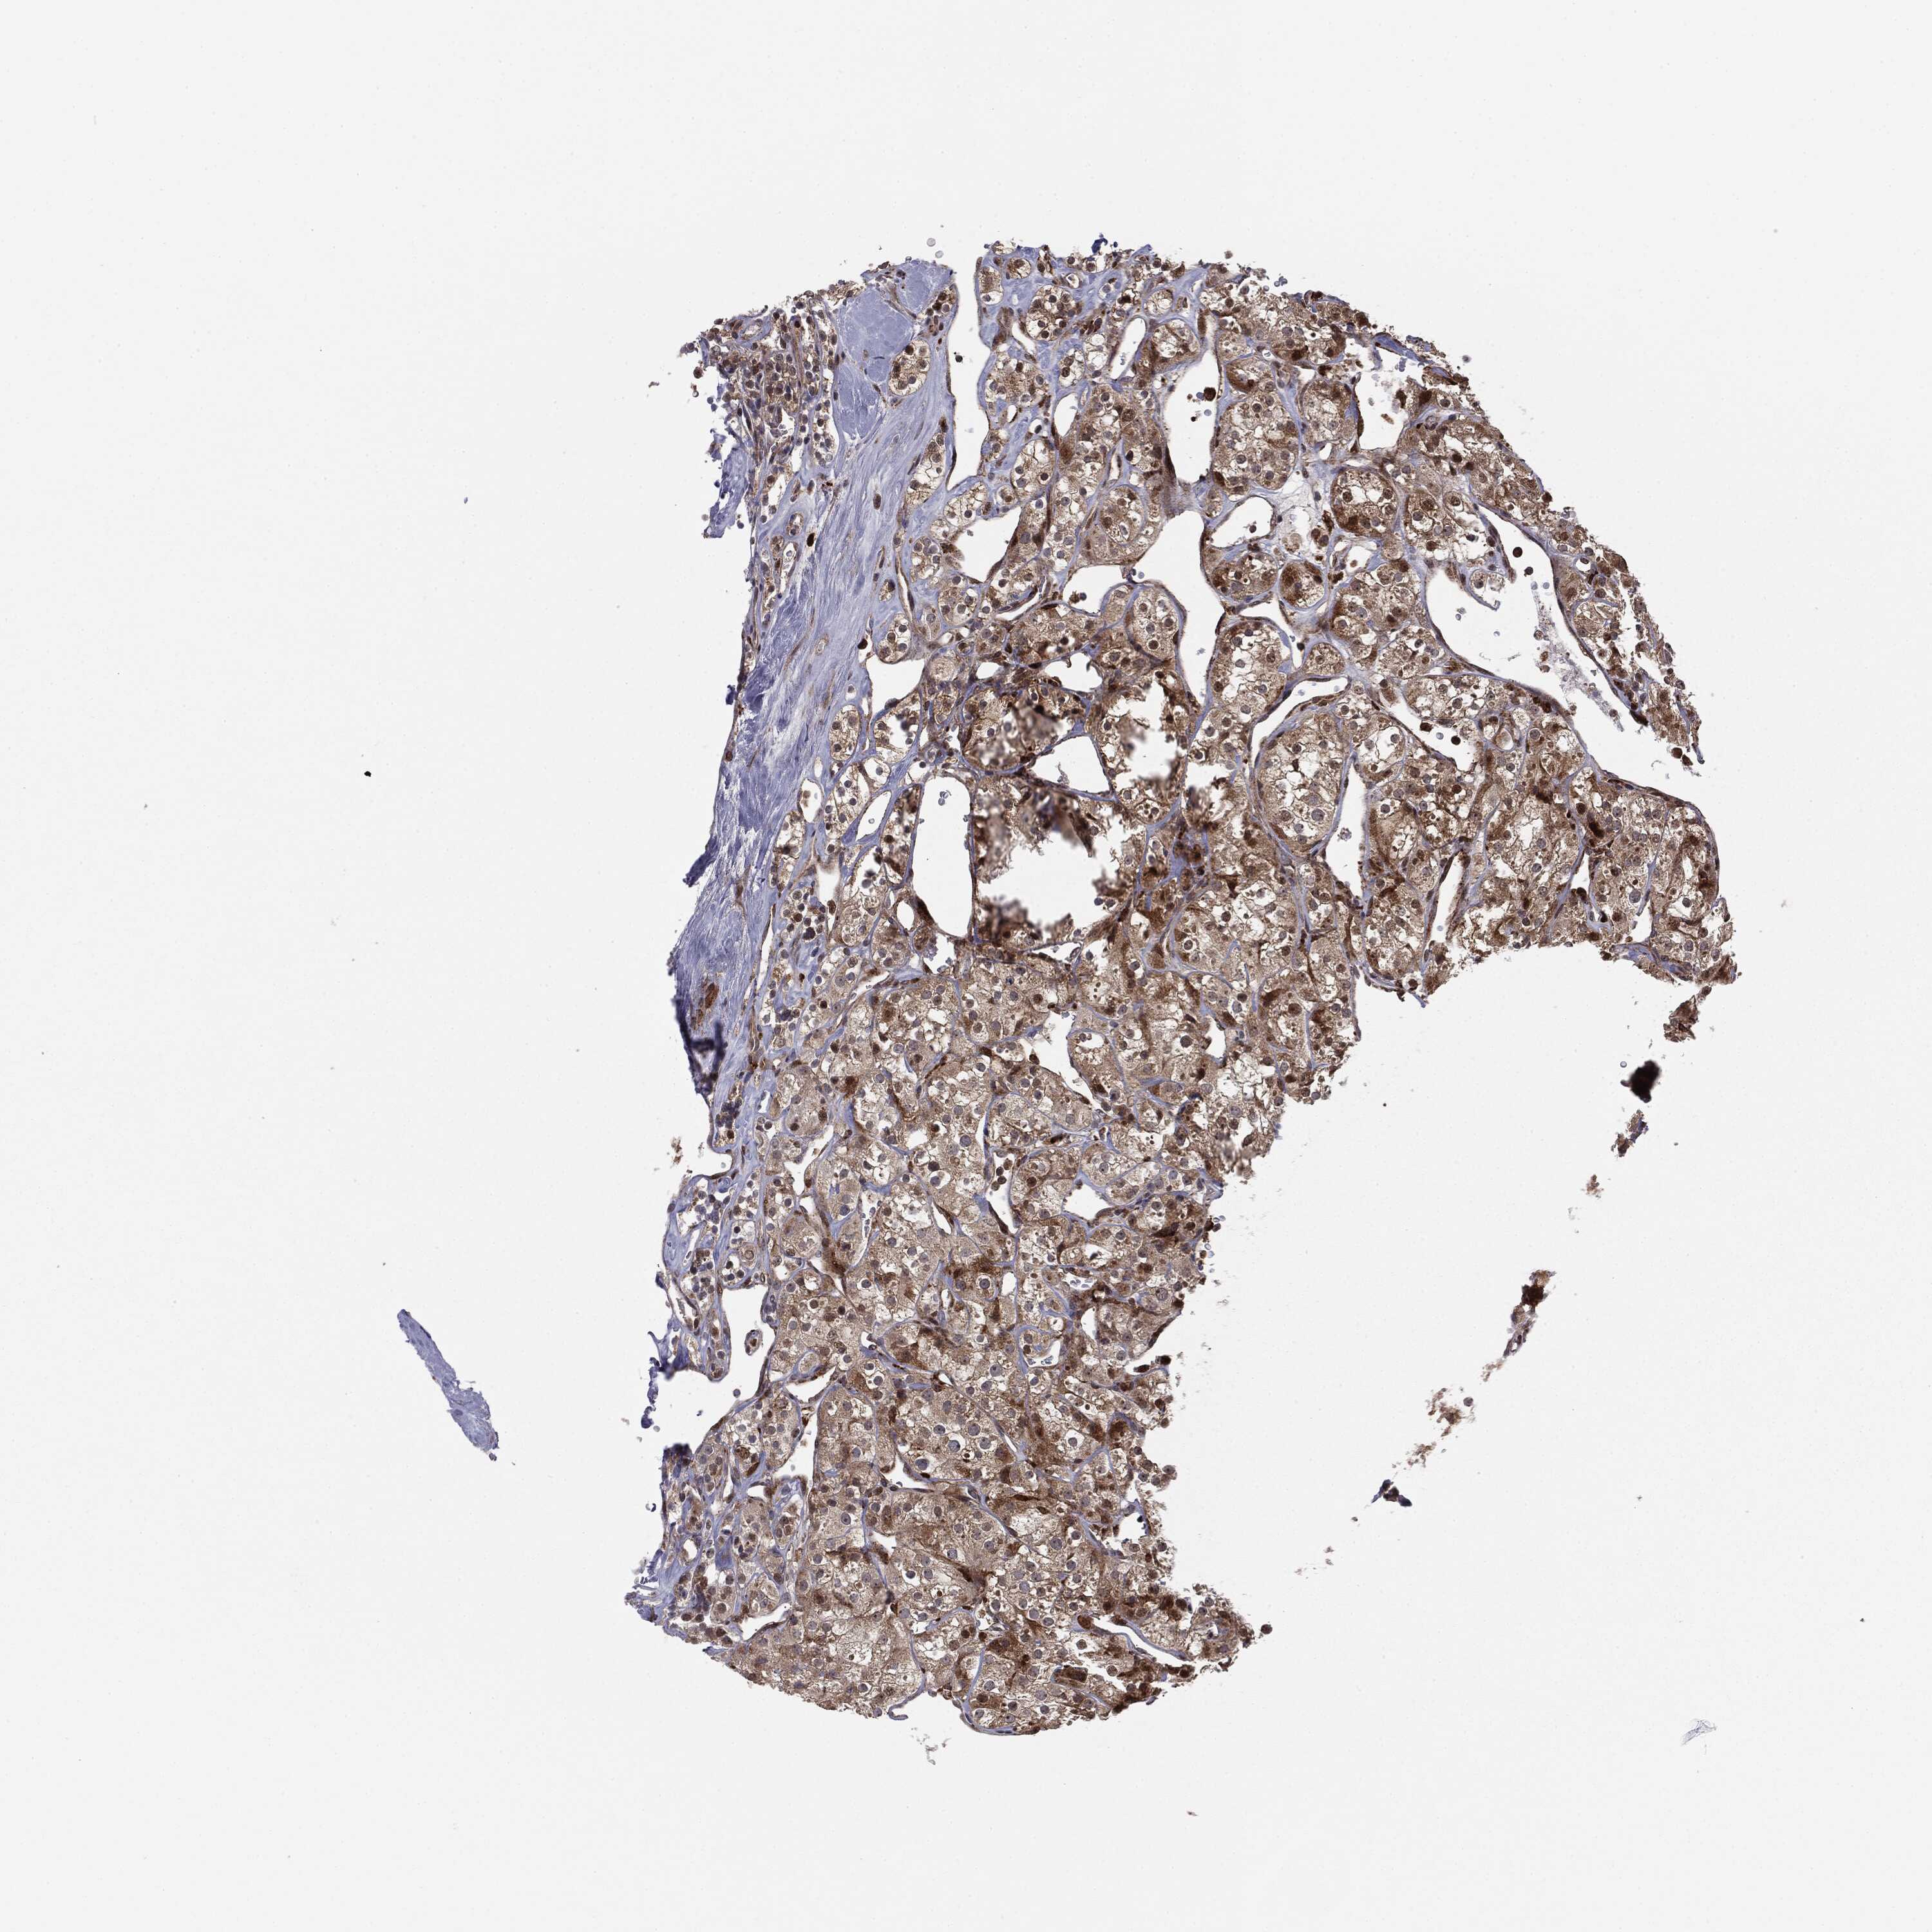

KIDNEY RENAL CLEAR CELL CARCINOMA (VALIDATION) - Interactive survival scatter ploti

The Survival Scatter plot shows the clinical status (i.e. dead or alive) for all individuals in the patient cohort, based on the same data that underlies the corresponding Kaplan-Meier plots. Patients that are alive at last time for follow-up are shown in blue and patients who have died during the study are shown in red.

The x-axis shows the expression levels (FPKM) of the investigated gene in the tumor tissue at the time of diagnosis. The y-axis shows the follow-up time after diagnosis (years). Both axes are complimented with kernel density curves demonstrating the data density over the axes. The top density plot shows the expression levels (FPKM) distribution among dead (red) and alive patients (blue). The right density plot shows the data density of the survived years of dead patients with high and low expression levels respectively, stratified using the cutoff indicated by the vertical dashed line through the Survival Scatter plot. This cutoff is automatically defined based on the FPKM cutoff that minimizes the p-score. The cutoff can be changed by dragging the vertical line or by entering a cutoff value in the square labeled "Current cut-off".

Under the Survival Scatter plot the p-score landscape (black curve; left axis) is shown together with dead median separation (red curve; right axis). Dead median separation is the difference in median mRNA expression between patients who have died with high and low expression, respectively. It is calculated as follows: median FPKM expression of dead patients with high expression - median FPKM expression of dead patients with low expression. This is intended to aid the user in visually exploring custom cutoffs and the associated p-scores and dead median separation.

Individual patient data is displayed and can be filtered by clicking on one or more of the category buttons on the top of the page. Categories describing expression level and patient information include: high, low, alive, dead, female, male and tumor stages. The scale of the x-axis can be toggled between linear and log-scale by clicking on the "x log" button. Mouse-over function shows TCGA ID, patient information and mRNA expression (FPKM) for each patient.

& Survival analysisi

Kaplan-Meier plots summarize results from analysis of correlation between mRNA expression level and patient survival. Patients were divided based on level of expression into one of the two groups "low" (under cut off) or "high" (over cut off). X-axis shows time for survival (years) and y-axis shows the probability of survival, where 1.0 corresponds to 100 percent.

PTEN is not prognostic in Kidney Renal Clear Cell Carcinoma (validation)

Best expression cut offi

Based on the FPKM value of each gene, patients were classified into two groups and association between prognosis (survival) and gene expression (FPKM) was examined. The best expression cut-off refers the FPKM value that yields maximal difference with regard to survival between the two groups at the lowest log-rank P-value. Best expression cut-off was selected based on survival analysis .

When clicking on this number, the vertical dashed line indicating cut-off, the interactive survival plot, and the Kaplan-Meier curve will be adjusted to show results based on the best expression cut-off.

: 26.73

TCGA RNA samplesi

RNA-seq data is reported as average FPKM (number Fragments Per Kilobase of exon per Million reads), generated by the The Cancer Genome Atlas (TCGA) .

Normal distribution across the dataset is visualized with box plots, shown as median and 25th and 75th percentiles. Points are displayed as outliers if they are above or below 1.5 times the interquartile range. FPKM values of the individual samples are presented next to the box plot.

Average pTPM 23.7

Number of samples 100